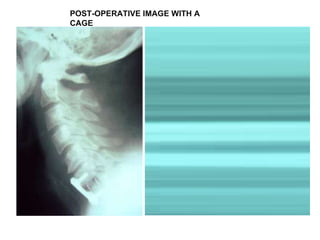

POST-OPERATIVE IMAGE WITH A CAGE

Post operative image The patient had an ACDF at C4/C5 and C5/C6. The kyphosis is corrected and hopefully will be maintained until fusion in the hard collar.  She will wear the collar for 3 months.

Clinically she recovered well from surgery and has been discharged home.  Her neurology has improved significantly with better sensation and increase in dexterity in the fingers.